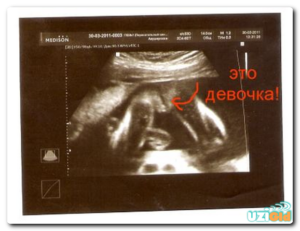

Вероятность ошибки на УЗИ определения пола ребенка может быть и в неточном определении половых признаков. Так, «увидеть» мальчика можно по половому члену и мошонке, а у девочки должны быть видны большие половые губы.

Зачастую врач может принять пальцы ребенка или пуповину за половой член, а отекшие половые губы девочки (случается часто) тоже можно принять за мошонку.

Кроме этого, плод может «спрятать» свои прелести и сжать плотно ножки, а врач подумает, что это девочка.